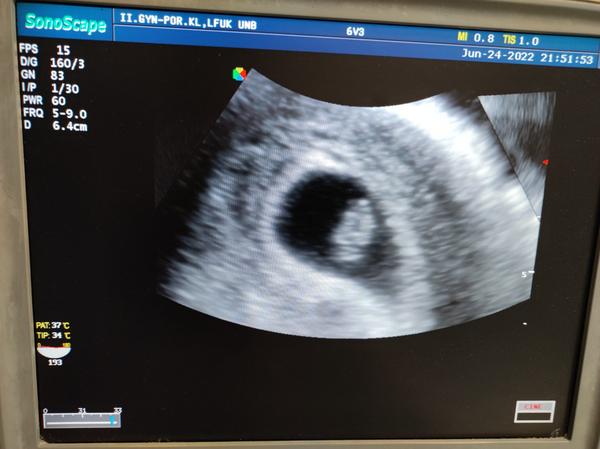

Sla som na wc a bum krv jasna cervena pri utreti. Tak som hned sla na pohotovost. Zlakla som sa a teda kedze mame ist to oznamit rodine chcela som vediet co sa deje. Nastastie ako tehotnu ma vysetrili okamzite.naozaj na prekvapenie som necakala ani minutu.lekar sice ma zdžubal ze som prisla hned pri nejakom slabuckom krvacani, ze mam vlozku cistu cistu,ze on by svoju zenu na pohotovost neposlal.ze keby vysetroval kazdu ktora zakrvaca tak by nerobil nic ine. No ale ja som nazoru ze radsej 100x zbytocne ako nieco zanedbat. Pri vysetreni videl kde to zakrvacalo niekde v krcku, ze vyzera byt vsetko ok. Dal mi pocut srdiecko, vyrastli sme o milimeter od stvrtku. Predpisal mi utrogestan.tak dufam,ze uz nebudem ani spinit ani nic...